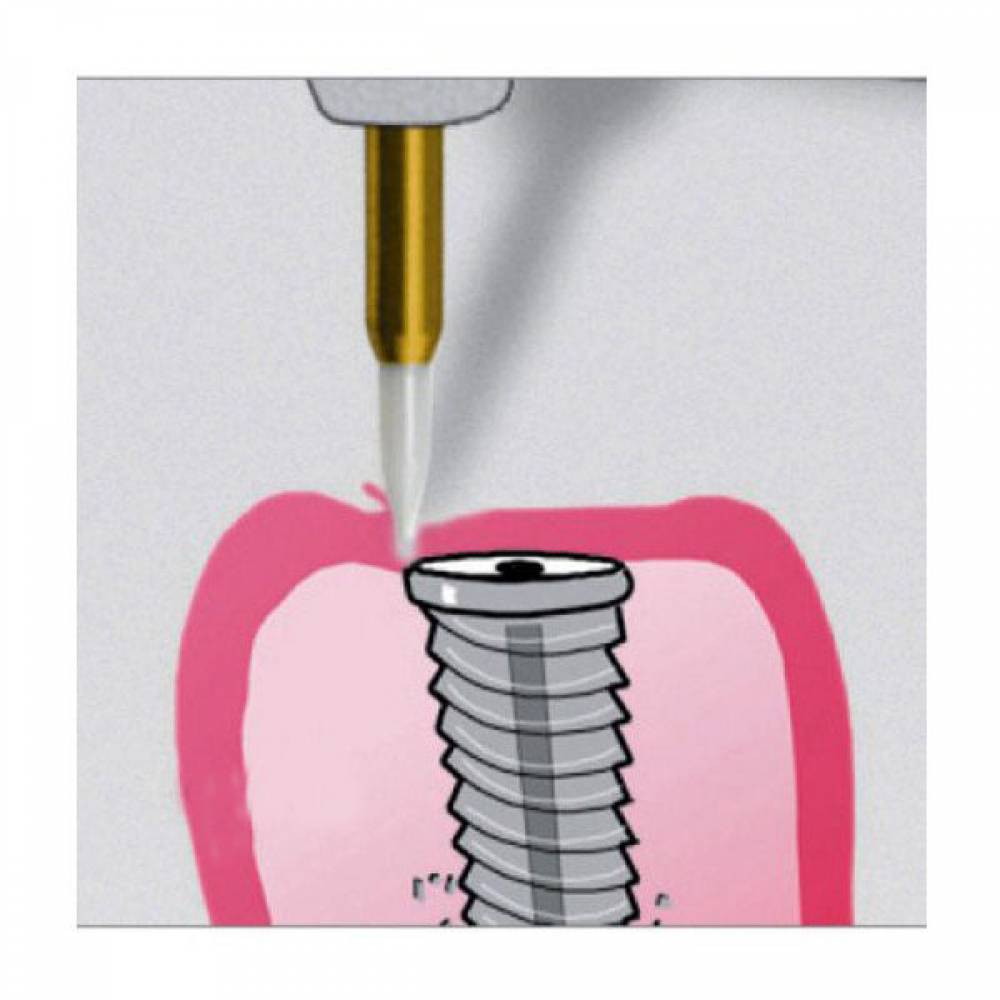

- کاربرد : برداشت لثه (Papilectomy) - برداشت بافت هاى مزاحم نشست روکش - باز کردن سالکوس قبل از گرفتن قالب - آشکار سازى بخش هاى از ایمپلنت که دیده نمى شود و دندانها نهفته

- ویژگی ها : انرژى جنبشى در بافت نرم به حرارت تبدیل مى شود .